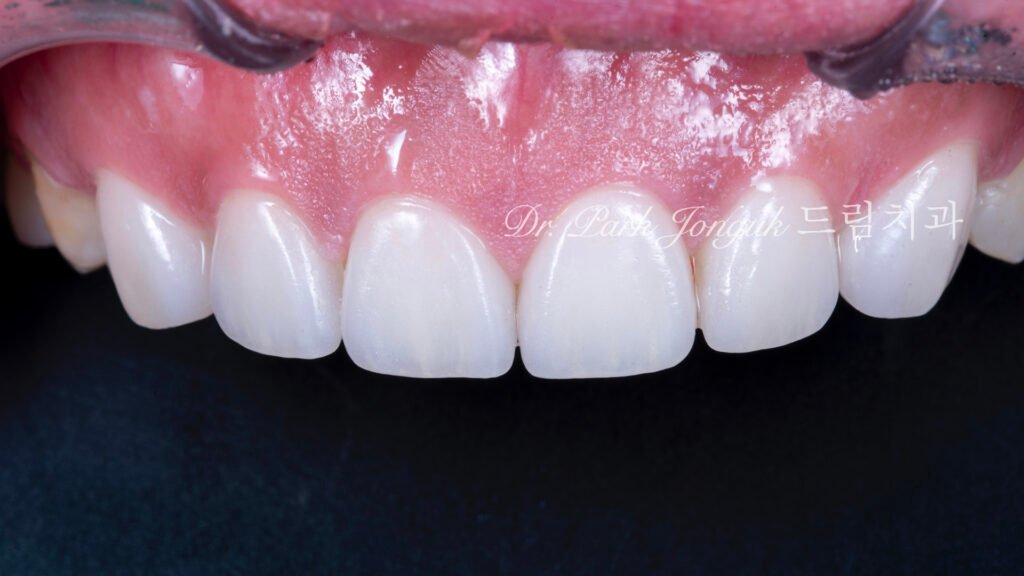

5. 최종 복원: 자연미의 극대화 (사진 6, 7, 8)

5.1 무삭제 라미네이트의 완성

[사진 6, 7, 8 참조] 0%의 삭제율로 완성된 최종 결과물입니다.

- 기능적 보호: 위산에 의해 약해진 치아 표면을 강도 높은 세라믹이 보호막처럼 감싸주어 추가적인 부식을 차단합니다.

- 광학적 재현: 기계로 깎아낸 Monolithic 방식이 아닌, 숙련된 기공사의 **핸드메이드 빌드업(Build-up)**을 통해 자연치 특유의 투명도와 질감을 재현했습니다.

- 심미적 조화: 교정으로 바르게 정렬된 치열 위에 정밀 설계된 라미네이트가 더해져, 부자연스러운 돌출감 없이 조화로운 미소를 완성했습니다.